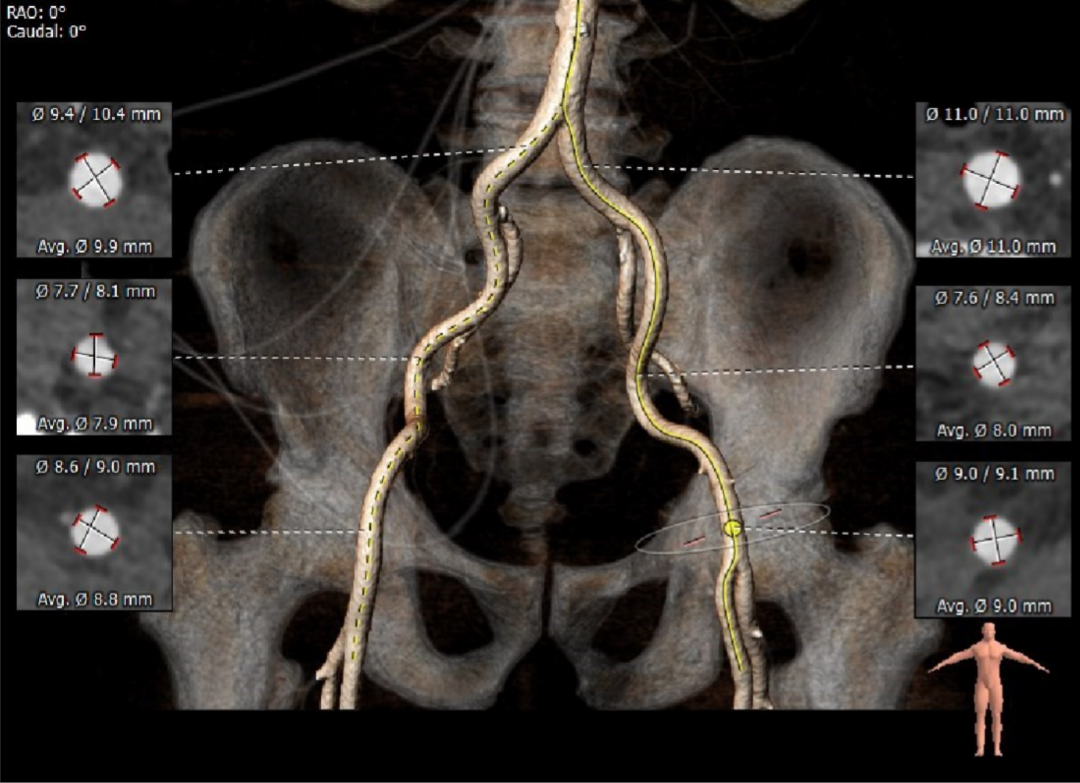

外周血管及主动脉弓解剖

双侧血管内径良好,所见主动脉血管壁见少量钙化形成。

患者双侧血管内径良好,术中选择右股动脉为主入路,左侧位辅入路。

主动脉瓣瓣环周长80.8mm,平均周长径 25.7mm,SOV:34.8mm*34.3mm*33.4mm,瓣叶增厚,瓣上见右无钙化嵴,瓣环水平夹角42°。